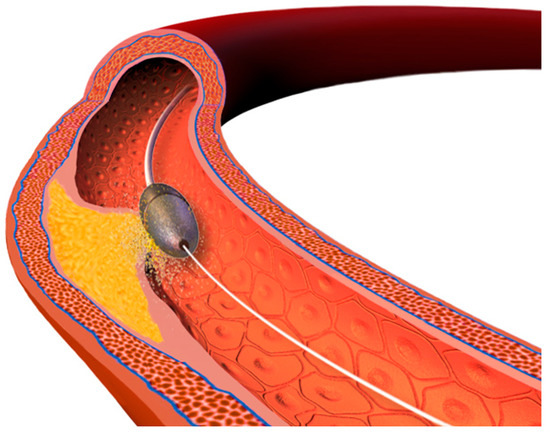

- Intravascular lithotripsy (IVL). The Shockwave Medical coronary IVL system is a fluid-filled balloon angioplasty catheter with two lithotripsy emitters incorporated into the shaft of the 12 mm long balloon (which is 0.014″ guidewire compatible). The balloon is delivered across the lesion and then expanded to 4 atm to enable the energy transfer. The fluid inside the balloon is vaporized using an electrical discharge from the emitters, which as a result creates a rapidly expanding and collapsing bubble that generates sonic pressure waves. The shockwaves pass through the balloon and into the calcified plaque, causing it to crack or fracture. The shockwaves from the lithotripsy emitters disrupt the structure of the calcified plaque without causing significant trauma to the surrounding healthy tissue. The goal is to modify the plaque, making the stent implantation easier. The system comes in 2.5, 3.0, 3.5, and 4.0 mm balloon diameters and should be sized 1:1 to the reference vessel diameter. When the balloon is positioned and expanded to 4 atmospheres, the cycle of 10 IVL pulses is delivered (which is followed by optional brief inflation to 6 atm). Up to 80 pulses per balloon or 120 with the latest generation Shockwave C2+ system can be delivered, with deflation between cycles to allow distal perfusion. The potential drawback of this technique is the bulkiness of the balloon which may hinder the delivery across the lesion. The Disrupt CAD studies demonstrated high procedural success and low 30 day major adverse cardiac event rate [38].